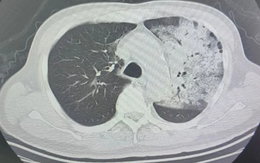

Người đàn ông trắng xóa nửa lá phổi vì 1 sai lầm nhiều người mắc khi dùng quạt điều hòa

Sống khỏe 2025-05-09T20:00:00Mới đây, Bệnh viện Nhân dân số 5 Thành Đô (Trung Quốc) đã tiếp nhận một trường hợp bệnh nhân nam có nửa lá phổi trắng xóa. Nguyên nhân đến từ 1 sai lầm khi sử dụng quạt điều hòa.